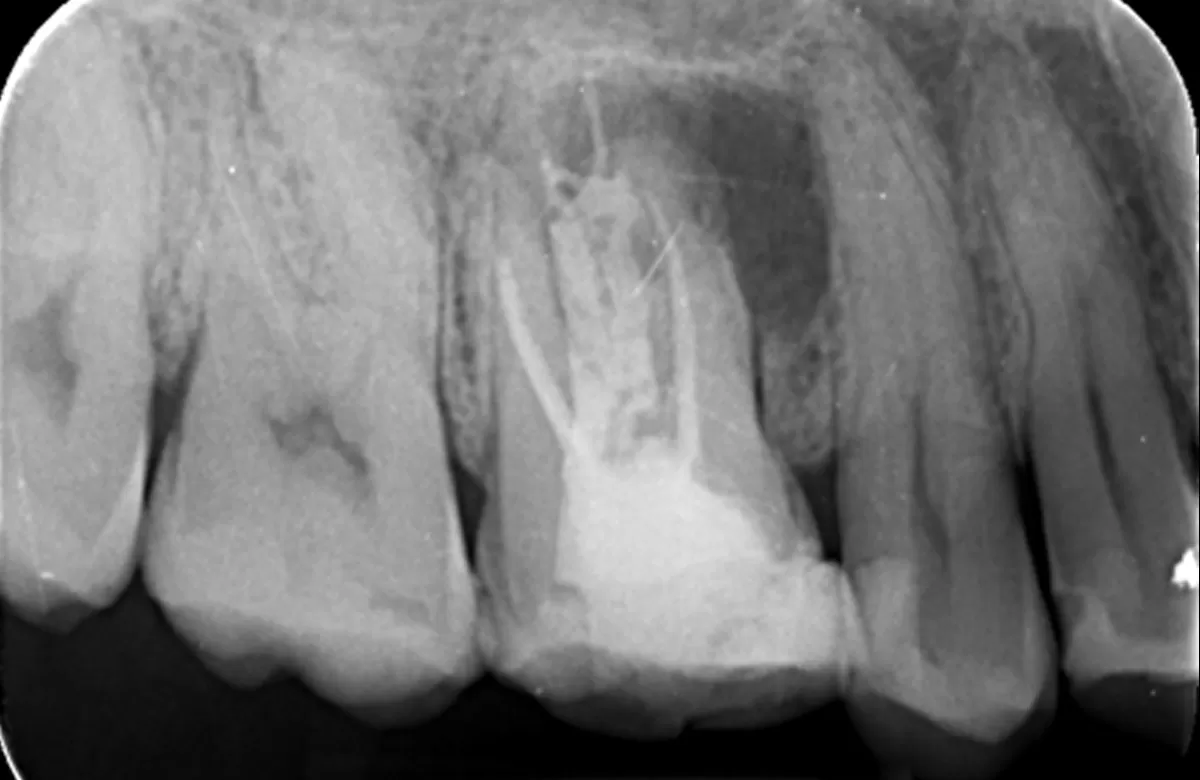

Pre obturation periapical radiograph of the tooth 16, checking cone length

Post obturation periapical radiograph showing obturation to length; right image: Review periapical radiograph showing increased bone infill around the mesiobuccal root

| PA demonstrates | Increased bone infill in comparison to post obturation PA taken 6 months prior |

| Review | Healing in progress |

| Patient reports | The tooth has been feeling good since treatment was completed. I can eat on that side again. |